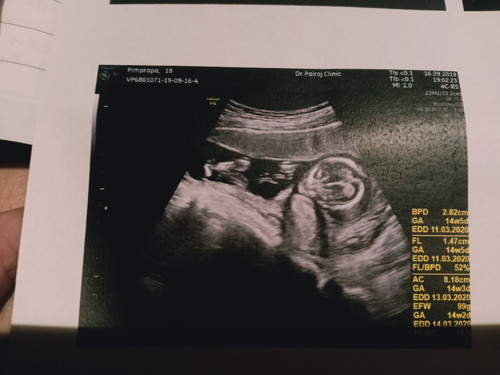

มีใครซาวด์น้องครั้งแรกแล้วเห็นเป็นตัวชัดแบบนี้มั้ยค่ะ แม่ตื่นเต้นมากๆเลยค่ะ นอนยิ้มไม่หุบเลยค่ะ น้องก็ดิ้นเก่งมากให้คุณหมอกับแม่ดูทุกมุมเลย??

บ้านนี้ก็ชัดมากจ้า เห็นเป็นตัวเป็นตนชัดเจน หัว ท้อง ขา แขน รก

คุณหมอบอกว่าน้องโตไว ค่ะ อายุครรภ์ในใบซาวด์ 14+5วีค แต่ในแอพบอกว่า14+2วีคจ้าแม่